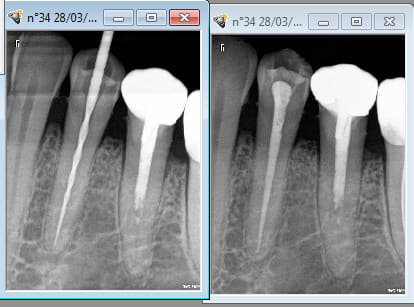

L'original et la copie cote à cote. -)